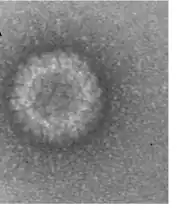

Coltivirus is a genus of viruses, belonging to the Reoviridae family, that infects vertebrates and invertebrates. It includes the causative agent of Colorado tick fever.[15]

The virus particle, like other coltiviruses, is about 80 nm in diameter and is generally not enveloped. The double-stranded RNA viral genome is about 20,000 bp long and is divided into 12 segments, which are termed Seg-1 to Seg-12. Viral replication in infected cells is associated with characteristic cytoplasmic granular matrices. Evidence suggests the viral presence in mature erythrocytes is a result of replication of the virus in hematopoetic erythrocyte precursor cells and simultaneous maturation of the infected immature cells rather than of direct entry and replication of CTFV in mature erythrocytes.[16]